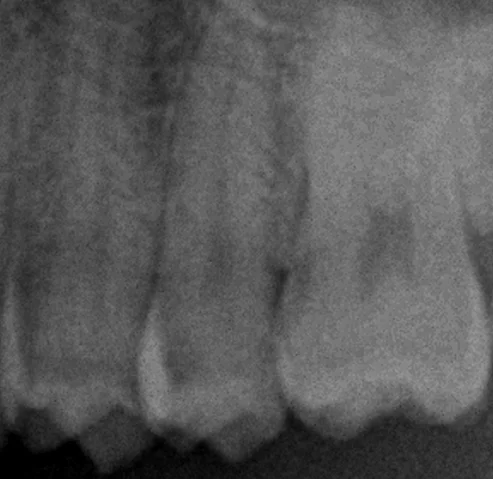

見た感じは全く普通に見えますが、実はレントゲン上で・・・

神経にかかりそうなくらいの大きな虫歯になっている状態でした。

このレントゲンの黒い部分が虫歯なのですが、全体が写る大きなレントゲン上でこれほどはっきりと見える虫歯は非常に大きいことが多いため、なかなか危ない状況であることが多いです。